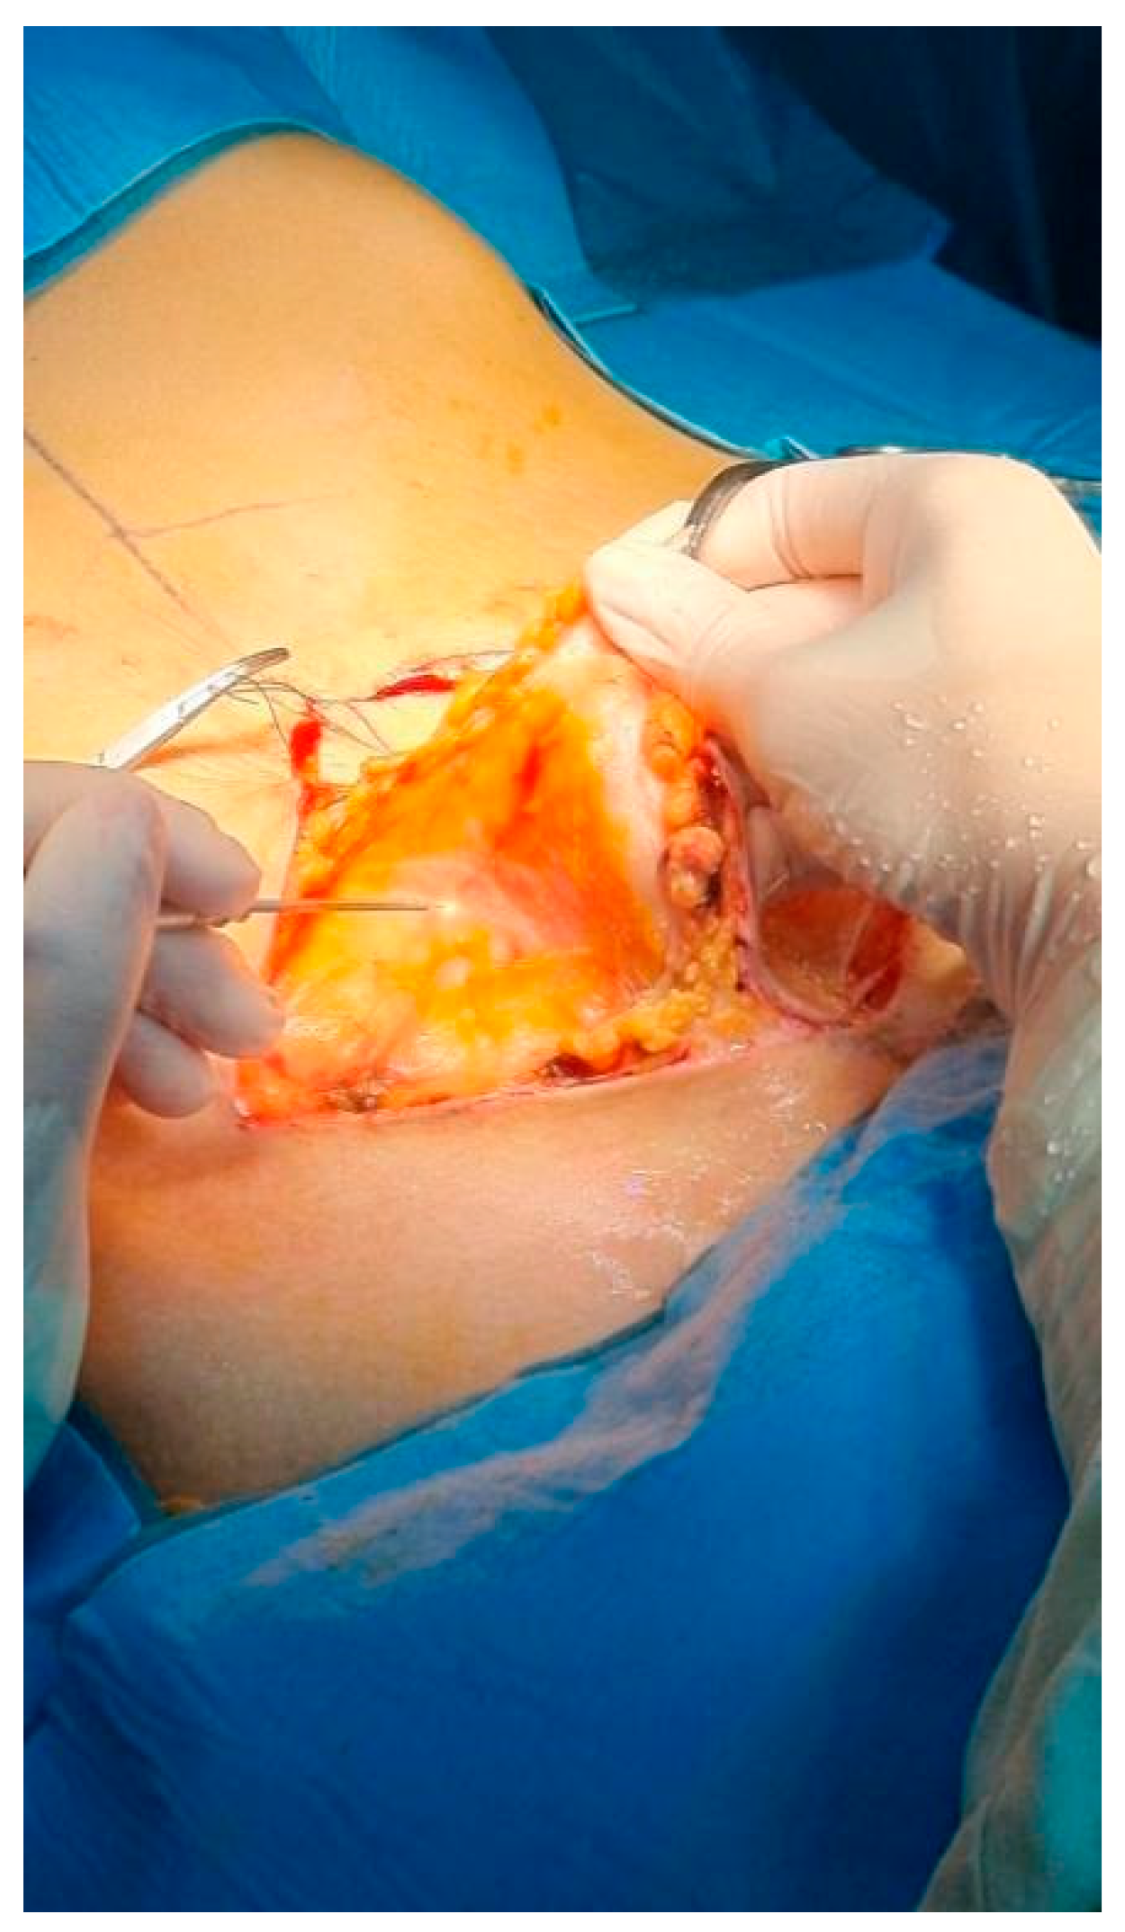

After optimizing the power and frequency parameters on rats, the laser was tested on a human cutaneous–subcutaneous flap excised during an abdominoplasty procedure. Biopsy samples of the skin and subcutaneous tissue were taken from this flap using different power settings: 15 W, 20 W, and 25 W. For comparison, an edge of the skin where an incision was made with a scalpel was also collected (Figure 1).

Figure 1. Clear dissection of the cutaneous–subcutaneous flap in abdominoplasty in the ex vivo phase.